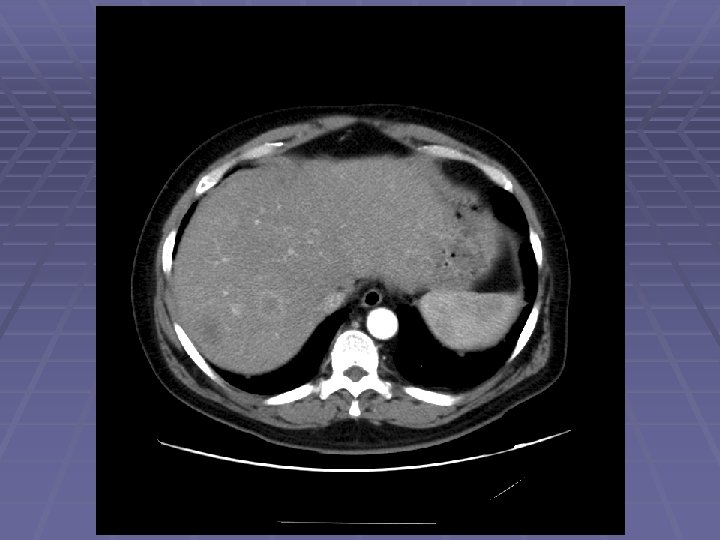

Hyperechoic Liver Masses

FNA of Hyperechoic Liver Mass